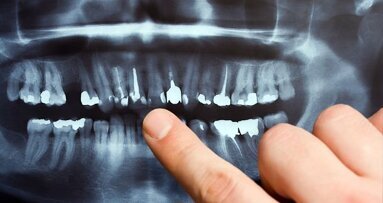

Jeśli problemy ze skórą są uporczywe, warto udać się do dermatologa, który na pewno znajdzie skuteczne rozwiązanie. Może się jednak okazać, że dermatolog odeśle pacjenta do dentysty. „Wciąż niewiele osób zdaje sobie sprawę z tego, że stan zdrowia zębów wpływa na stan zdrowia całego organizmu. Zepsute zęby powodują choroby serca, płuc, problemy z zębami można także wyczytać z wyglądu skóry twarzy. Dlaczego tak się dzieje? Otóż w przypadku zepsutych zębów mamy do czynienia ze skupiskiem bakterii. Gdy stan zapalny w jamie ustnej jest poważny, tzn. taki, że wymaga np. leczenia kanałowego lub są to długotrwałe zapalenia przyzębia to bakterie rozprzestrzeniają się na cały organizm, wywołując tzw. chorobę odogniskową” – tłumaczy lekarz dentysta Bartosz Nowak z Gliwic .Gdy przyczyną trądziku jest zepsuty ząb, a nie np. zmiany hormonalne czy łojotok, to wypryski najczęściej pojawiają się w okolicy ust, na brodzie i kościach szczęki.

Ząb nie musi boleć, by powodował problemy ze skórą twarzy. „Jeśli ząb boli, to zazwyczaj jest to początkowy sygnał tego, że z zębem dzieje się coś niedobrego. Dużo bardziej niebezpieczne dla zdrowia są sytuacje, gdy ząb nie boli, a mimo to wymaga natychmiastowego leczenia lub nawet usunięcia. Pozostawione korzenie czy martwe zęby często nie dają żadnych sygnałów bólowych, a stanowią siedlisko bakterii, które przez krwiobieg są przenoszone do innych narządów i powodują stan zapalny lub niepotrzebnie obciążają dany organ” – tłumaczy dr Nowak.

Wszystkie te problemy mają źródło w braku dbania o zdrowie zębów. „Do takiej sytuacji dochodzi w przypadku nieleczonej próchnicy. Bakterie przenikają w głąb miazgi zęba, a potem do korzenia i dochodzi do obumarcia zęba. W środku namnażają się bakterie gnilne, tzw. beztlenowe i mimo, że ząb nie boli, to jednak przez ukrwioną kość szczęki, z którą jest połączony bakterie przenikają do innych organów, powodując zakażenia lub stany zapalne. W przypadku uzupełniania ubytku martwego zęba nie wystarczy założyć zwykłej plomby. Konieczne jest leczenie kanałowe, tzw. endodontyczne, lekarz usuwa wtedy zniszczoną miazgę zęba, dezynfekuje ząb wraz z korzeniem i usuwa bakterie. Samo założenie plomby by tu nie pomogło, bo bakterie by zostały” – wyjaśnia dentysta. To samo dotyczy nieusuniętych korzeni, które bezwzględnie powinny zostać usunięte. „Wielu pacjentów sądzi, że wraz z utratą zęba doszło także do usunięcia bakterii próchnicowych. Nic bardziej mylnego. Pozostawiony korzeń jest także niebezpieczny dla zdrowia. Nawet nie do końca wyrznięte zęby mądrości mogą być siedliskiem bakterii, często wokół nich pojawiają się obrzęki i torbiele, a z powodu utrudnionego dostępu są znacznie bardziej narażone na występowanie próchnicy” – przestrzega dr Nowak.